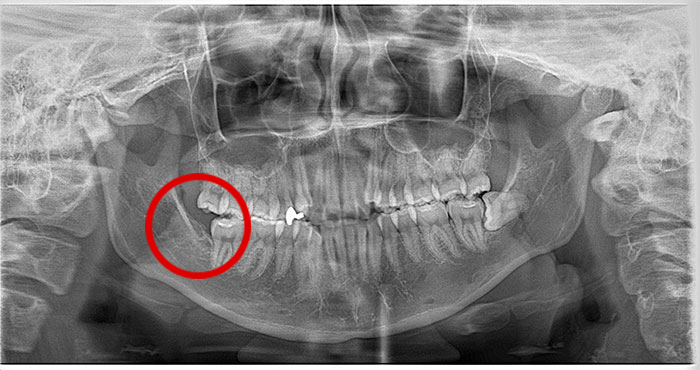

横になった親知らずの症例

Before

After

真横になった親知らずを抜歯したレントゲン写真です。